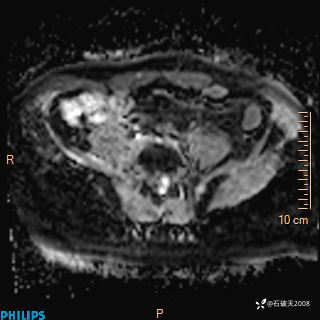

2023年3月份MRI影像

增强轴位